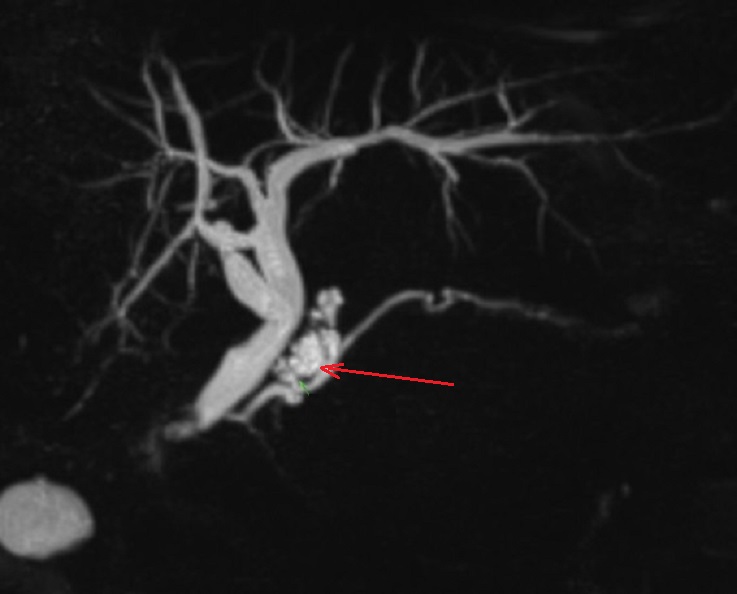

Image radiologique Wirsungo-cholangio IRM

d'une TIPMPde type canaux secondaire du corp pancreas avec image de kyste

multiple , polylobulaire ( fleche rouge ) en

communication avec la CPP . Image radiologique du

canal choledoque et des voies biliaire

intrahepatique sont en vue tres nette . |